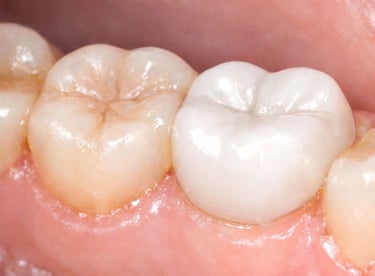

Tooth Colored Filling in Shyamal, Ahmedabad

Tooth-colored fillings are used to restore decayed or broken teeth while maintaining a natural appearance. These fillings blend seamlessly with your tooth color and help preserve your smile.

All images shown here are real tooth colored filling cases treated at our clinic with patient consent.

At Shree Dental Care, cosmetic fillings are placed carefully with a focus on comfort, precision and long-term durability. We ensure minimal tooth cutting and natural-looking results.

If you are looking for aesthetic tooth colored filling in Shyamal, Ahmedabad, you can book an appointment with our clinic.